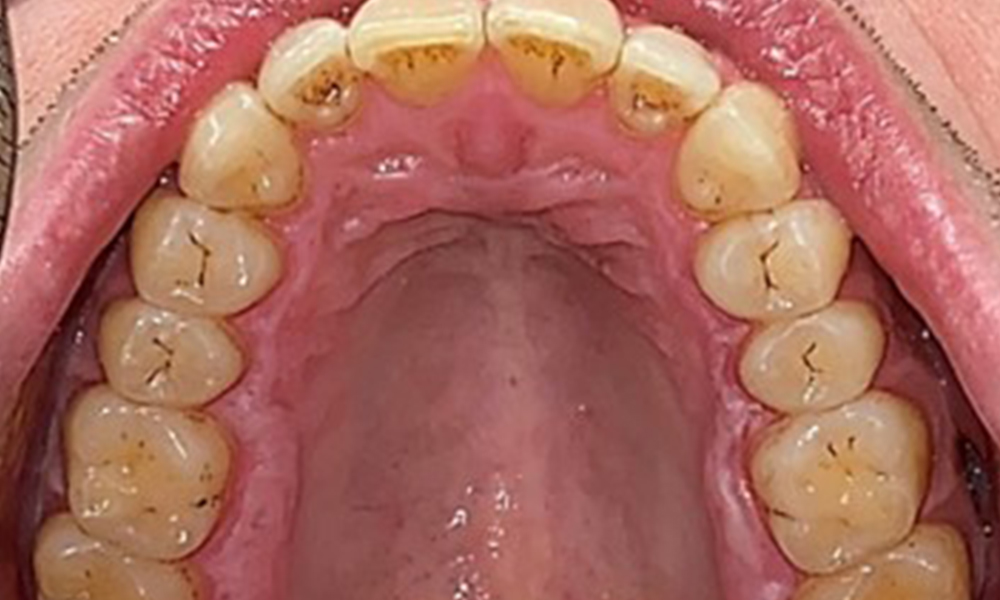

Observații la nivel dentar

Pacientul prezintă o dentiție completă, cu 28 de dinți. Se remarcă eroziuni și atriții. (Fig. 4, Fig. 5). Datorită bruxismului, timp de mulți ani, pacientul a purtat gutieră pe timp de noapte. Eroziunile sunt cauzate de consumul prelungit de băuturi izotonice. Nu au fost observate pierderi osoase de natură parodontală sau carii active.

Se observă o dentiție adultă completă, fără carii sau pierderi osoase vizibile radiologic (Fig. 6). Pierderi cuspidale și de smalț evidente radiologic, cu precădere pe 36 și 37.